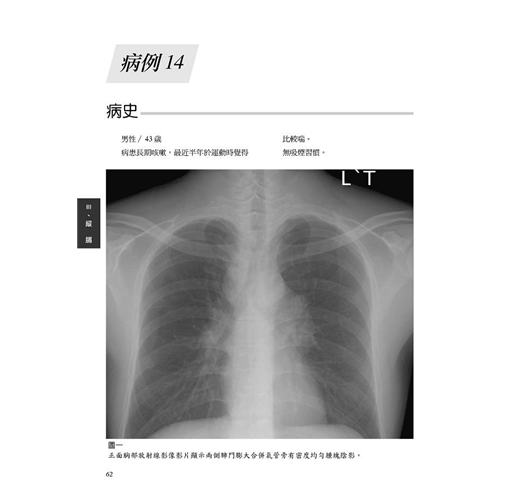

病例14 類肉瘤(Sarcoidosis) 62